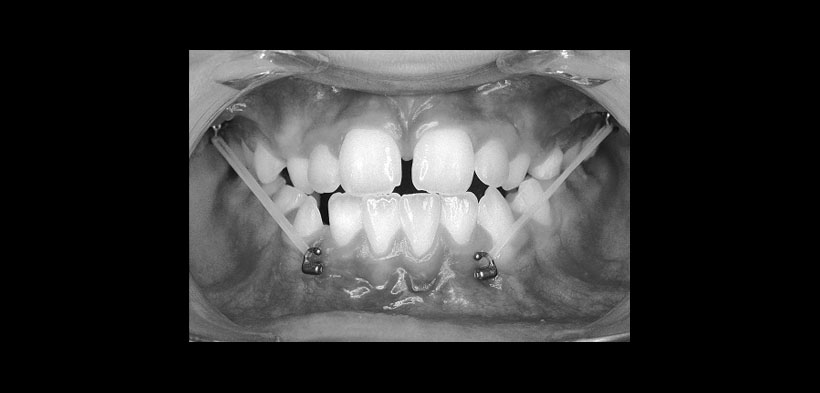

Figura 1 Tracción elástica se aplica desde las tablas óseas vestibulares superiores a las tablas óseas vestibulares inferiores durante 24 horas al día durante un periodo de 1 año.